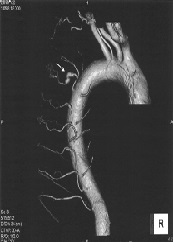

Coil Embolization for a Ruptured Intercostal Artery Aneurysm Complicated with Neurofibromatosis Type 1

Hiroshi Hashiyada*, Yuriko Takeuchi, Kembu Nakamoto, Kazuya Yoshida, Toshiyuki Fujii, Hiroshi Maruta, Motohiro Takeshige